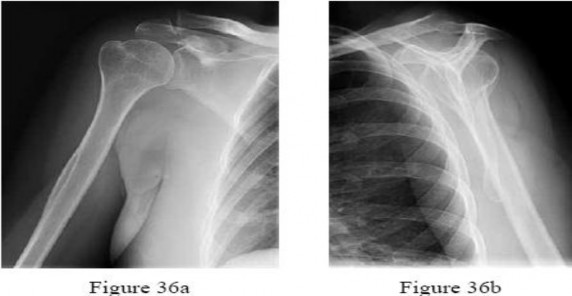

A 72-year-old female sustains a 3-part proximal humerus fracture. She is indicated for an open reduction and internal fixation (ORIF) with a locking plate via a deltopectoral approach.

To avoid injury to the axillary nerve, what is the generally accepted 'danger zone' for plate placement distal to the tip of the greater tuberosity?

Explanation

The axillary nerve courses horizontally across the anterior aspect of the upper humerus. The average distance from the superior aspect of the greater tuberosity to the axillary nerve is approximately 5 to 7 cm. When placing a lateral locking plate for proximal humerus fractures, dissecting or passing the plate in this zone puts the nerve at high risk. Care must be taken to either slide the plate under the nerve or clearly identify and protect it.